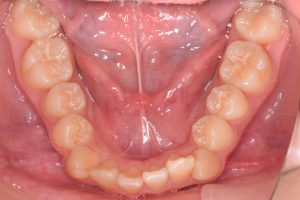

下あご

0000000005

0000000027

0000000078